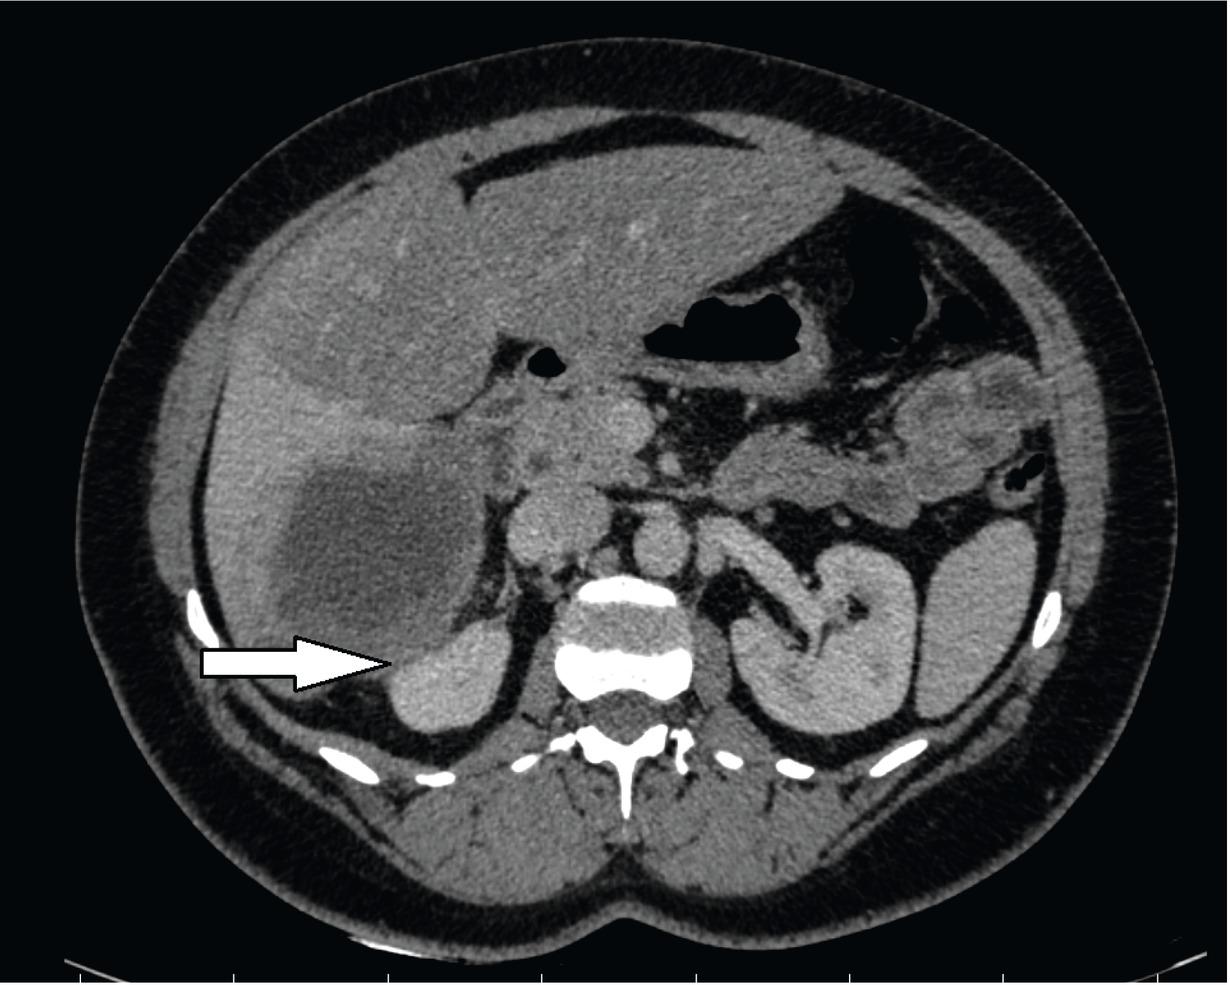

Fig. 2